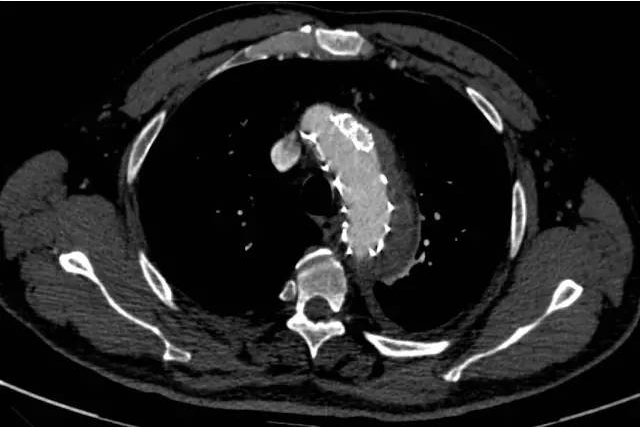

手术过程非常顺利,王兵副院长亲自操刀,整个手术过程仅耗时2小时。术后在施敏护士长带领的护理团队精心的护理下,患者恢复良好,术后复查CTA(见下图),主动脉支架位置良好,破口封堵满意,无内漏,两个“烟囱”支架通畅,无脑梗塞、肢体及内脏缺血等并发症的发生。现在大家悬着的心完全放了下来,叮嘱患者一定要控制血压,按时随访,复查CTA评估支架的情况。

主动脉、左颈总动脉及左侧锁骨下动脉支架

术后复查CTA